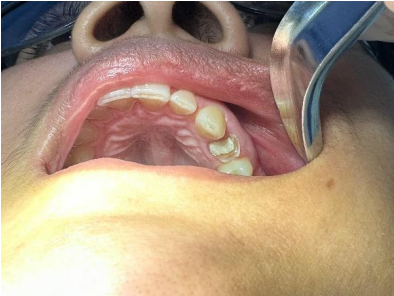

Paciente: E.B.S, sexo feminino, idade 34 anos, compareceu a clínica odontológica para início de tratamento reabilitador do elemento 24 (primeiro prémolar superior esquerdo, que havia sido submetido a um tratamento endodôntico, com necessidade de reforço do remanescente coronário e a confecção da coroa total protética fixa, para reestabelecer a função e estética.

1ª Sessão: Inicialmente foi realizado a desubturação parcial dos canais radiculares, mantendo o selamento apical com o comprimento mínimo para garantir o sucesso endodôntico. Em seguida, foi realizada a prova e ajuste do pino de fibra de vidro, o qual apresentou boa adaptação, dessa forma, foi feita a anatomização dos condultos e cimentado com cimento resinoso dual, considerando o protocolo adesivo adequado: condicionamento ácido, aplicação dos adesivos compatíveis e inserção do cimento nos canais, garantindo o preenchimento adequado e ausência de bolhas, após essa etapa, foi realizada a fotoativação e fotopolimerização completa, o núcleo coronário foi preenchido com resina composta para criar um remanescente anatômico que possibilitasse a confecção do preparo. Na sequência foi realizado o preparo para receber a coroa total, respeitando os princípios da retenção, resistência e espessura do material. Para a moldagem funcional a gengiva foi afastada com o fio retrator, e executada com silicona de condensação (pesada e leve), garantindo a cópia fiel dos limites cervicais. Posteriormente foi confecciada uma coroa provisória em resina composta, devidamente com a oclusão ajustada e protocolos de polimento, proporcionando conforto, e estética satisfatória à paciente. A cor foi escolhida e o molde juntamente com o registro de mordida foram encaminhados ao laboratório para que fosse confeccionada a coroa de teste clínico, e na sequência a coroa definitiva.

Figura – Imagem inicial